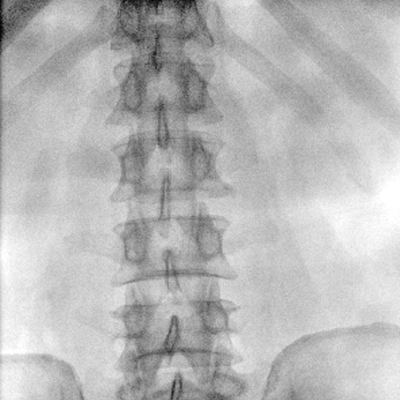

臨床適用科室:骨科、普通外科、矯形外科、創(chuàng)傷外科、泌尿外科、脊柱外科、疼痛外科、消化科、婦科等科室。

大尺寸動態(tài)平板探測器,高DQE、低噪聲、圖像清晰。采用多分辨率圖像增強(qiáng)處理技術(shù),不同部位不同圖像處理算法,滿足客戶多樣化的需求。